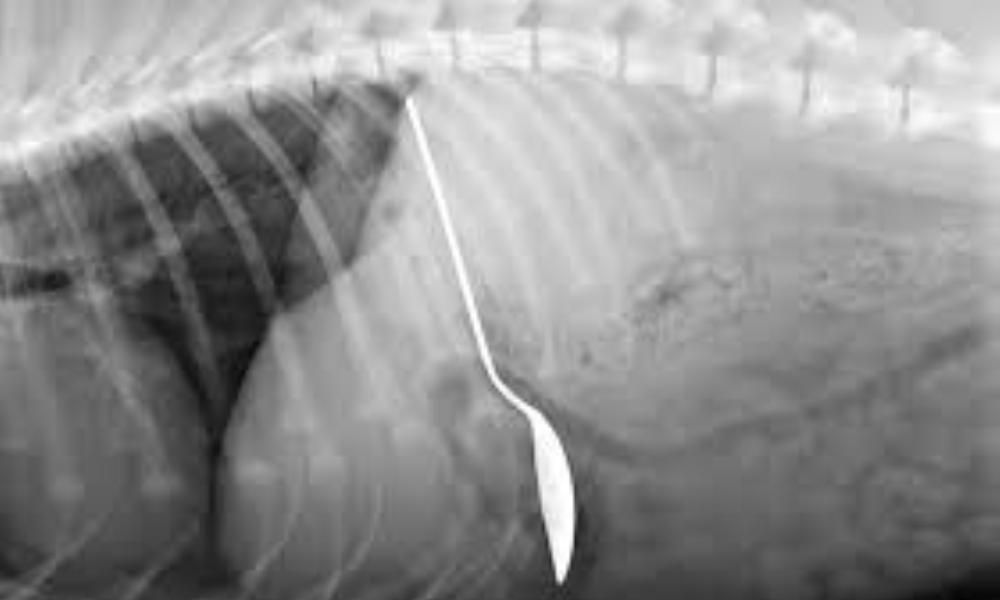

29-летний житель Актау обратился к врачам с жалобами на боль в желудке. Специалисты с помощью рентгенографии брюшной полости нашли у него инородные тела размерами 18, 16 и 15 сантиметров. Оказалось, что в его желудке - куски арматуры длиной 5-6 см и ручка от алюминиевой ложки, пишет InAktau.

С помощью видеоэзофагогастродуоденоскопии инородные тела извлекли из организма. Это были куски арматуры разной длины, а также ручка от алюминиевой ложки. Операция длилась полчаса и прошла успешно, - рассказал врач-эндоскопист Бауыржан Танауов.